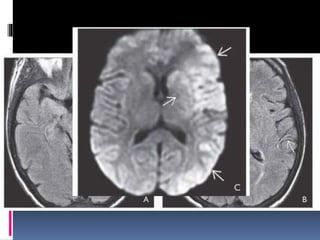

DWI shows multiple foci of restricted diffusion at the GM-WM junctions of both

hemispheres.

NECT scan ina patient with infected mitral valve, decreasing mental status shows 2 hemorrhagic foci at the GM-WM junctions of both occipital lobes. (Right) Scan through the corona radiata shows additional hemorrhagic foci . Findings suggest multiple septic emboli. DWI shows multiple foci of restricted diffusion at the GM-WM junctions of both hemispheres.